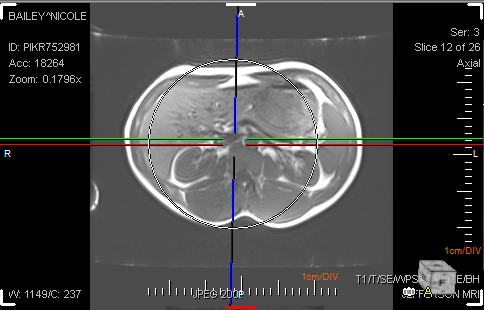

At any given time, one of the Viewports can be selected as the Controlling viewport with a click of a mouse. The remaining three view boxes display the cutting planes related to the three axes in the controlling viewport. All three axes are joined in the center. The Oblique option allows the X and Y axis to rotate. If this option is checked off, the user will not be able to move the axis. The option is checked by default. The horizontal and vertical axes are perpendicular to each other and make up the double cutting plane. The third axis is independent of the other two axes and can be rotated around the center point, calle the single cutting plane. As the cutting planes are rotated and translated, the remaining three view boxes update to reflect the new cuts. While the Vertical axis is used to rotate the image across the y-axis, two slide bars at the right hand and at the bottom of the image can be used.

The MPR mode allows to view the image in three views i.e. Axial, Coronal or Sagittal. If the user wishes to perform an operation on the image in one view, the change will be visible in all the three views simultaneously. To scroll through images, simply use the central wheel button of the mouse.

To adjust the slab width, click and drag the dotted lines on the image to adjust the slab width. The cursor will change to a small hand symbol when the slab width is being adjusted.

The adjustment of slab width is in real time i.e. you will see the impact of this change in other view boxes while you are adjusting the width in the current view.